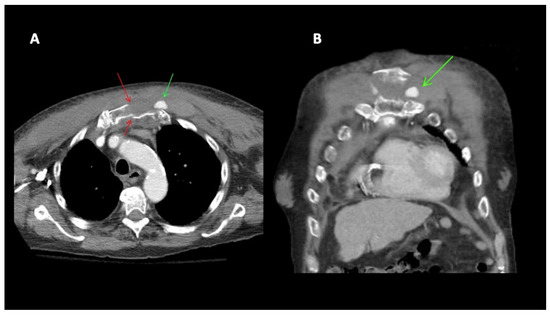

This case concentrates on the persistent left superior vena cava (PLSVC), a rare vascular anomaly which contributes to central venous catheter (CVC) misplacement. A 72-year-old woman with renal insufficiency presented to the hospital with recurrent bleeding from her permanent CVC device placed in the right common jugular vein. An initial attempt to replace the device was unsuccessful, necessitating the placement of a secondary catheter in the left jugular vein. Shortly after the procedure, the patient developed swelling of the face and neck. Further diagnostic imaging, including a chest radiograph and computed tomography (CT), revealed CVC misplacement in the PLSVC and coronary sinus, thrombosis of the common jugular vein, and a posterior mediastinal hematoma. Conservative therapy of the mediastinal hematoma was implemented and proved effective in this case. A temporary CVC was inserted into the left femoral vein. Two months later, the catheter underwent further dysfunction and a decision was made to place a long-term permanent CVC via the right femoral vein. The patient is currently awaiting an arteriovenous fistula for dialysis use. This case emphasizes the importance of radiological techniques for CVC procedural placement, as well as the detection of congenital abnormalities. Providers regularly placing CVCs should have an in-depth knowledge of the possible complications and potential anatomical variations, especially as seen in high-risk patients. Full article

Figure 1